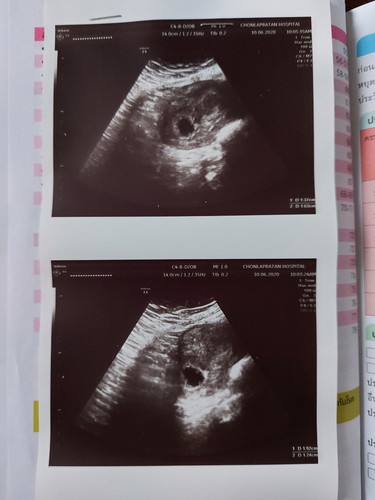

วันนี้ไปฝากท้องมาคะ ตอนนี้ได้9Wแล้ว แต่ไม่เห็นน้องเลย เห็นแค่ถุงที่อยู่ในมดลูก(หมอก็เรียกไม่ถูกเหมือนกัน555 หมอวัยรุ่น) คุณแม่บ้านไหนเคยเจอเคสแบบนี้มั๊ย เรากังวลมากเลย กลัวไม่มีน้อง?

รอซาวด์ใหม่อีกสัก 1-2 วีคค่ะ หมอนัดแล้วใช่ไหมคะ ไม่ต้องกังวลค่ะ บางบ้านก็เจอน้องช้า ☺️